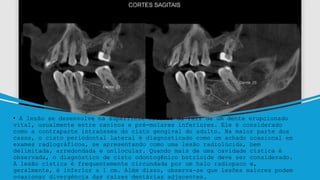

• A lesão se desenvolve na superfície lateral da raiz de um dente erupcionado

vital, usualmente entre caninos e pré-molares inferiores. Ele é considerado

como a contraparte intraóssea do cisto gengival do adulto. Na maior parte dos

casos, o cisto periodontal lateral é diagnosticado como um achado ocasional em

exames radiográficos, se apresentando como uma lesão radiolúcida, bem

delimitada, arredondada e unilocular. Quando mais de uma cavidade cística é

observada, o diagnóstico de cisto odontogênico botrioide deve ser considerado.

A lesão cística é frequentemente circundada por um halo radiopaco e,

geralmente, é inferior a 1 cm. Além disso, observa-se que lesões maiores podem

ocasionar divergência das raízes dentárias adjacentes.

• A lesãose desenvolve na superfície lateral da raiz de um dente erupcionado vital, usualmente entre caninos e pré-molares inferiores. Ele é considerado como a contraparte intraóssea do cisto gengival do adulto. Na maior parte dos casos, o cisto periodontal lateral é diagnosticado como um achado ocasional em exames radiográficos, se apresentando como uma lesão radiolúcida, bem delimitada, arredondada e unilocular. Quando mais de uma cavidade cística é observada, o diagnóstico de cisto odontogênico botrioide deve ser considerado. A lesão cística é frequentemente circundada por um halo radiopaco e, geralmente, é inferior a 1 cm. Além disso, observa-se que lesões maiores podem ocasionar divergência das raízes dentárias adjacentes.